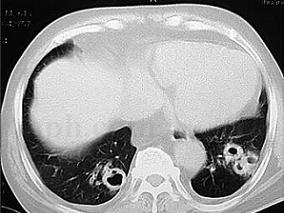

1小时条评论一、病史摘要 患者,男性,27岁,因反复咯血26天于2009年10月5日入院。患者于2009年9月9日修车时突然出现咯血,量约250ml(1~2次),鲜红色,无发热、咳嗽、咳痰、气促及胸痛等不适,就诊于当地县人民医院,胸片示右下肺不张(图120‐1),予以垂体后叶素等药物治...